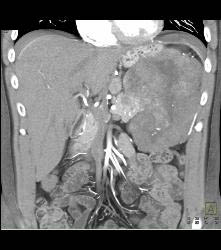

GIST Tumor With Ulceration